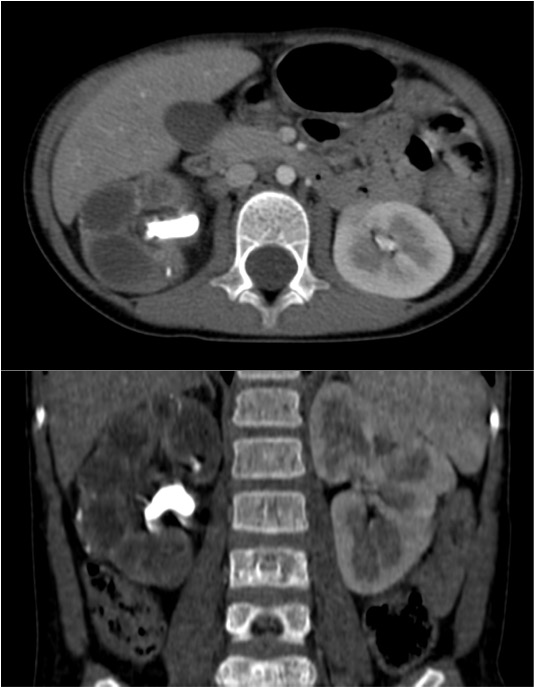

Tomografía Computarizada:

Es la técnica de elección por dos razones:

- Alta especificidad y definición de los hallazgos que permiten confirmar el diagnóstico.

- Descartar afectación extrerrenal y Planificación quirúrgica.

Estos hallazgos son altamente sujestivos de PNXG:

- Aumento difuso del tamaño y pérdida del contorno renal.

- Litiasis coraliforme: cálculo central en pelvis renal contraída (también puede existir calcificaciones intraparenquimatosas). La TC es la mejor técnica para identificar las litiasis.

- Riñón no funcionante (pobre o nula eliminación del medio de contraste en el riñón afectado).

- Cálices renales dilatados (áreas hipodensas) de apariencia multiloculada que se asemeja a una «pata de oso».

- También pueden darse abscesos o áreas de necrosis parenquimatosa.

- Cambios inflamatorios que excede los límites del riñón y genera colecciones periféricas o extensión hacia vísceras vecinas. Pueden darse abscesos en el psoas y fístulas (cutáneas o colónicas) que indican progresión de la enfermedad.

Aunque el área de hipoatenuación que se extiende desde la pelvis renal contraída hasta los cálices renales puede sugerir una hidronefrosis, la baja atenuación corresponde más bien a tejido inflamatorio antes que a líquido (la nefrostomía percutánea no siempre se lleva a cabo).

Veamos un caso.

Paciente mujer de 62 años que acude por decaimiento general con fiebre y dolor en flanco izquierdo. Ingresa en UVI por signos de sepsis

Nos cuenta antecedentes de pielonefritis e hidronefrosis crónica.

Hallazgos en imagen:

Estos hallazgos pueden ser dificiles de interpretar, ya que una paciente con hidronefrosis crónica y litiasis en el uréter puede haber sufrido una obstrucción que origina un cuadro de dolor en FRI con ruptura de cálices y colección extra axial. Otra probabilidad puede ser un angiomiolipoma que ha roto un aneurisma y ha producido un sangrado. También podríamos estar ante una pionefrosis aunque dada dada la clínica, los antecedentes y al observar los hallazgos en TC podríamos establecer la sospecha de pielonefritis xantunogranulomatosa con alta probabilidad. La confrimación vendrá dada con la nefrostomía y estudio de anatomía patológica.